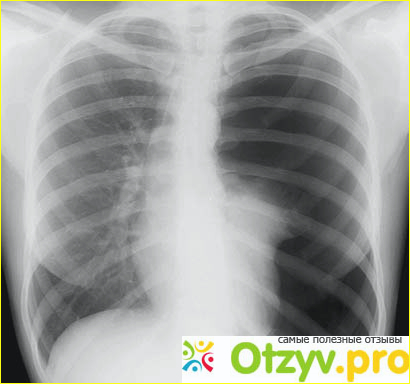

Меня сопровождали друзья до необходимого кабинета, на улице уже было очень темно и я понимал, что рабочее время то уже заканчивается, на что собственно врач мне сказал, что я видите ли задерживаю ее, а ничего, что это ее работа. И кто-то ночью тоже должен дежурить. Она начала меня опрашивать, говорить было очень сложно, дыхание замедлялось, было не стабильным. Потом я стал заполнять анкету и наконец-то она меня направила на прохождение рентгена, там то собственно мне и поставили диагноз - спонтанный гидропневматоракс. Очень много жидкости и воздуха находилось в моем левом легком, точнее в плевральной полости. Врач начал со мной довольно в грубой форме разговаривать, мне это конечно же не понравилось, но я тогда не уделял этому особое внимание. На пункции легкого она не присутствовала, хочу поблагодарить персонал, который довольно грамотно и за короткие сроки сумел выкачать из плевральной полости достаточное количество жидкости и воздуха. Ко мне привязали баночку, куда стекались остатки - дренаж плевральной полости. И врач мне не объяснил, как пользоваться шлангом. В один момент мне захотелось попить воды и я даже пару шагов не сделал к шкафчику, как упал на пол и разбил не только себе нос, но еще и саму банку. Я потерял сознание и хорошо, что медсестра на звук среагировала.